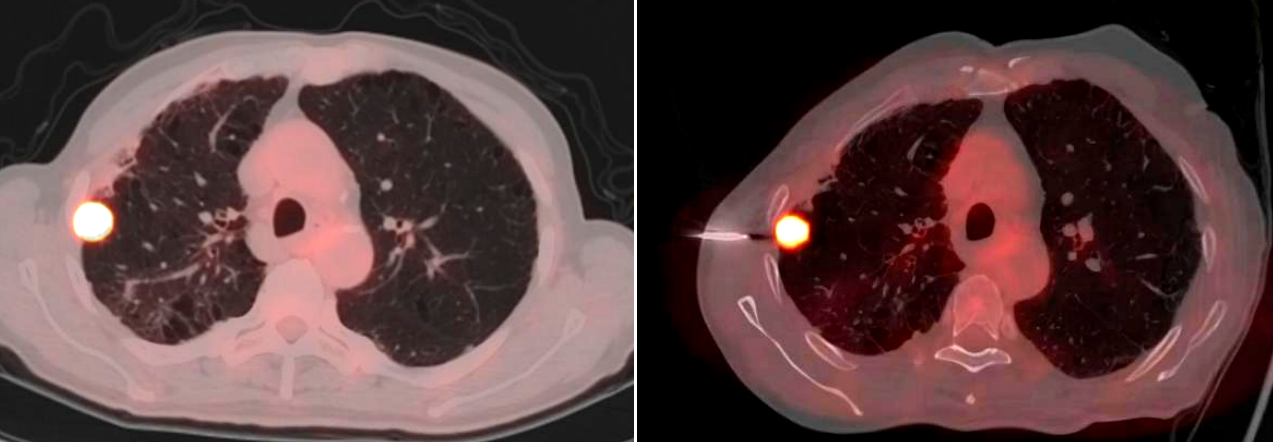

成功开展了云南省首例PET/CT引导下的肺肿瘤穿刺活检术,为云南省肺部疾病的精准诊断再添助力。

手术当日,PET/CT中心的方龙栋主管技师首先为患者进行了详细的扫描,精准确定了肿瘤的位置和代谢活跃区域。随后,在胸外科医生严密的监测下,精准地将穿刺针经皮穿刺进入患者肺部,准确抵达肿瘤部位,成功获取了病理组织样本。整个手术过程顺利,患者术中及术后均未出现明显并发症。从PET/CT的精准成像,到胸外科医生的穿刺操作,再到病理科的准确诊断,体现了胸外科、PET/CT中心、病理科多学科团队的高效配合和专业能力。

PET/CT中心郝金钢副教授表示,此次云南省首例PET/CT引导下肺肿瘤穿刺活检术的成功开展,标志着财神捕鱼 在肺部疾病影像诊断方面的更进一步。与传统穿刺活检技术相比,PET/CT引导下的穿刺活检具有更高的精准度,能够显著提高病理诊断的阳性率,减少不必要的穿刺次数,降低患者的痛苦和风险。这一技术的应用,将为更多肺部疾病患者带来精准诊断和个性化治疗的希望。